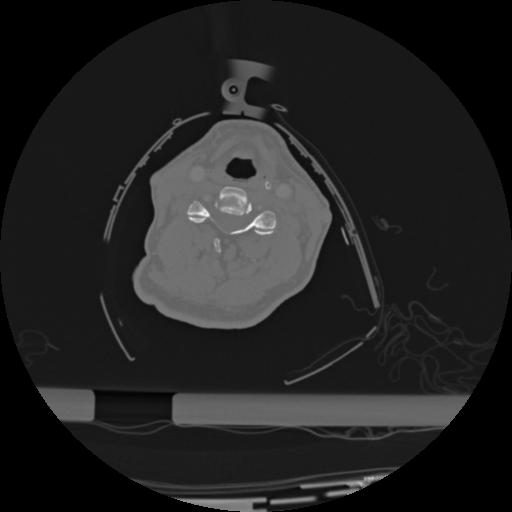

22 ANGIO,CE,Vol,0.5,ANGIO,,